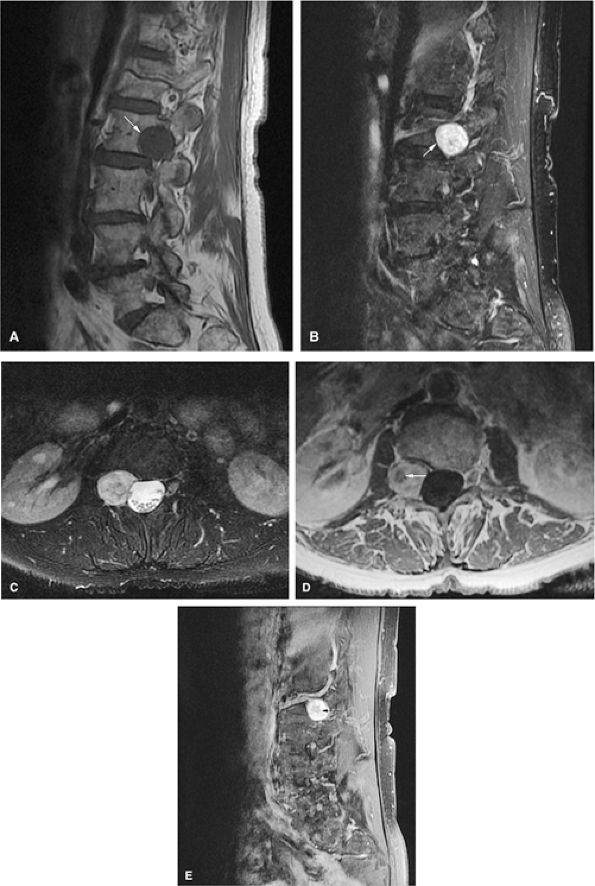

![]() |

FIGURE 14-15 ● Osteoblastoma arising in the posterior elements of the L2 vertebra is demonstrated on sagittal (A) and axial (B) fat-suppressed T2-weighted fast spin-echo images. Fluid–fluid levels are present (arrows). The tumor is isointense to muscle (arrow) on the axial T1-weighted image (C) and demonstrates enhancement (arrow) following intravenous injection of gadolinium (D). Note the mass effect upon the spinal canal from the tumor.